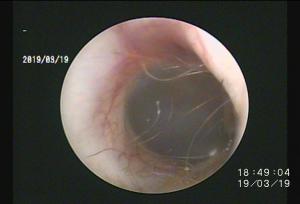

一言で外耳炎と言っても・・原因は様々・・ですよね。

繰り返す外耳炎で意外と知られていない原因に「ゴミの蓄積」があります。

ゴミと言っても成分は細菌、脂、汗、毛、炎症細胞・・などなどが混じって形成されています。

そのゴミが鼓膜付近に蓄積していると、点耳薬や洗浄(一般的は)は効果を十分に発揮できません。

まずはこの汚れをしっかり除去することが重要ですね。

この除去はやはり大変です・・鼓膜があるのと、耳の道が狭いこと(晴れている場合も多い)、動くのでそもそも無理・・

道内では珍しい耳道内視鏡治療を積極的に行っています(麻酔下で初めに除去することでその後のケアが楽になるので他施設で行っていない施術を当院では取り入れています)

これがなかなか技術が必要ですが、処置後の経過が良いことがモチベーションになります!

この耳道内視鏡はあまり知られていませんが、お困りの症状にあった処置ができますので今後もアナウンスしていきます!

道内遠方の方も来院されますので、遠くの方でお困りの症状がございましたらまずはご連絡くださいませ。